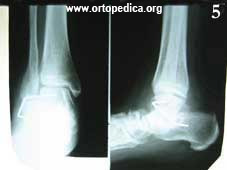

5. Рентгенограмма через 2 месяца после операции подтаранного артродеза

Рентгенограмма в боковой проекции после операции подтаранного артродеза Рентгенограмма после операции подтаранного артродеза Рентгенограмма через 2 месяца после операции подтаранного артродеза